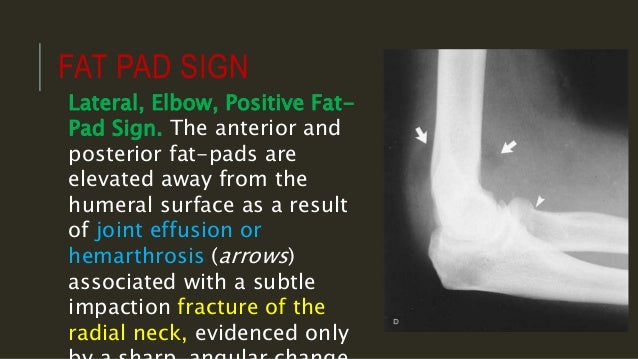

On an elbow x ray a fat pad sign suggests an occult fracture. Capitellum of the humerus with the ra.

Elbow anatomy xray. On a normal elbow x ray only a small stripe of an anterior fat pad should be visible. The elbow is a complex synovial joint formed by the articulations of the humerus the radius and the ulna. No posterior fat pad should be seen.

Continue with the mr. Injuries around the joint can produce a joint effusion which will displace the fat pads making them more visible. Gross anatomy articulations the elbow joint is made up of three articulations 23.

Both anterior and posterior fat pad signs exist and both can be found on the same x ray. Typically widely displaced due to unopposed pull of triceps. Use the mouse to scroll or the arrows.

It is caused by displacement of the fat pad around the elbow joint. Knee shoulder shoulder arthrogram ankle elbow wrist hip contact. Common represent 10 of all adult upper extremity fractures.

The posterior fat pad is not visible soft tissue of the triceps muscle is not separated from the posterior edge of the humerus.